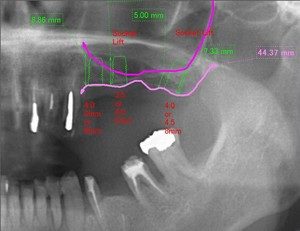

上顎の奥歯のインプラントを行うにあたって骨の量が不足してみえましたので上顎洞に骨の移植を行いました。